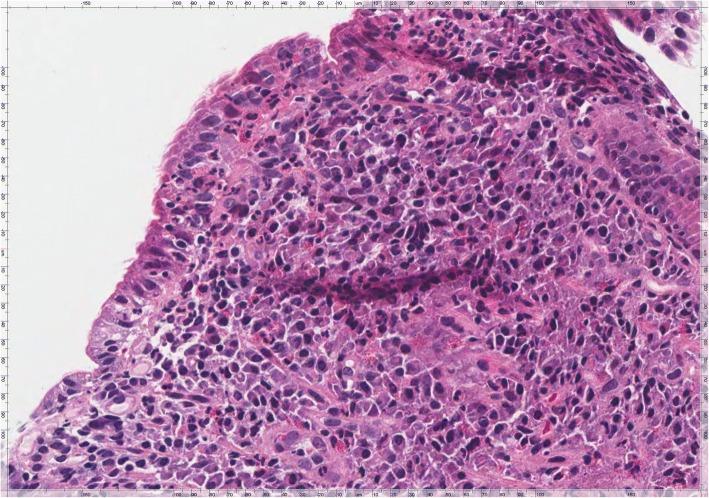

A 42-year-old outpatient woman without previous significant gastrointestinal diseases, was referred with dyspeptic symptoms, fatigue and mild diarrhea from 4 months. Her first investigations including immunoglobulin A (IgA) anti-tissue transglutaminase antibodies (anti-tTG) and stool parasitological and cultural analysis were negative. An esophagogastroduodenoscopy (EGDS) showed no mucosal alteration. But histology demonstrated a Helicobacter Pylori (HP) pan-gastritis while duodenal mucosa showed villous atrophy consistent with a diagnosis of CD Marsh type 3b. While on gluten-free diet (GFD) the patient didn't experience any improvement of symptoms. Duodenal biopsies were then reviewed showing the presence of trophozoites of Giardia on the luminal surface of the duodenal wall and at the same time, a second stool examination revealed the presence of trophozoites and cysts of Giardia. Treated with metronidazole, 500 mg twice daily for 6 days the patient reduced diarrhea after few days. After about 2 months of GFD she was invited to discontinue it. At the same time stool examination was repeated with negative results. She subsequently performed eradication for Hp with triple therapy (Pylera®). Around 6 months later, the patient did not complain any gastrointestinal symptoms. Serological tests were normal and at a follow-up EGDS, duodenal mucosa had normal histology with normal finger-like villi and absence of Giardia trophozoites.

一名42岁门诊女性,既往无重大胃肠道疾病,因4个月来的消化不良症状、疲劳和轻度腹泻前来就诊。她最初的检查,包括免疫球蛋白A(IgA)抗组织转谷氨酰胺酶抗体(抗tTG)以及粪便寄生虫学和培养分析均为阴性。食管胃十二指肠镜检查(EGDS)未发现黏膜改变。但组织学显示幽门螺杆菌(HP)全胃炎,而十二指肠黏膜显示绒毛萎缩,符合CD Marsh 3b型诊断。在采用无麸质饮食(GFD)期间,患者症状未得到任何改善。随后复查十二指肠活检,显示十二指肠壁腔面存在贾第虫滋养体,同时,第二次粪便检查发现贾第虫滋养体和包囊。患者接受甲硝唑治疗,每日两次,每次500 mg,共6天,几天后腹泻减轻。在GFD约2个月后,她被要求停止该饮食。同时重复粪便检查,结果为阴性。随后她接受了三联疗法(Pylera®)根除HP。大约6个月后,患者未再抱怨任何胃肠道症状。血清学检查正常,在随访EGDS时,十二指肠黏膜组织学正常,有正常的指状绒毛,且无贾第虫滋养体。